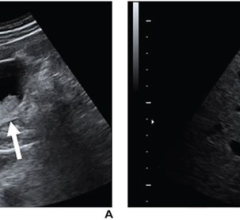

March 15, 2024 — Screening-detected radial scars without atypia at core-needle biopsy (CNB) have a low upstaging rate to ...